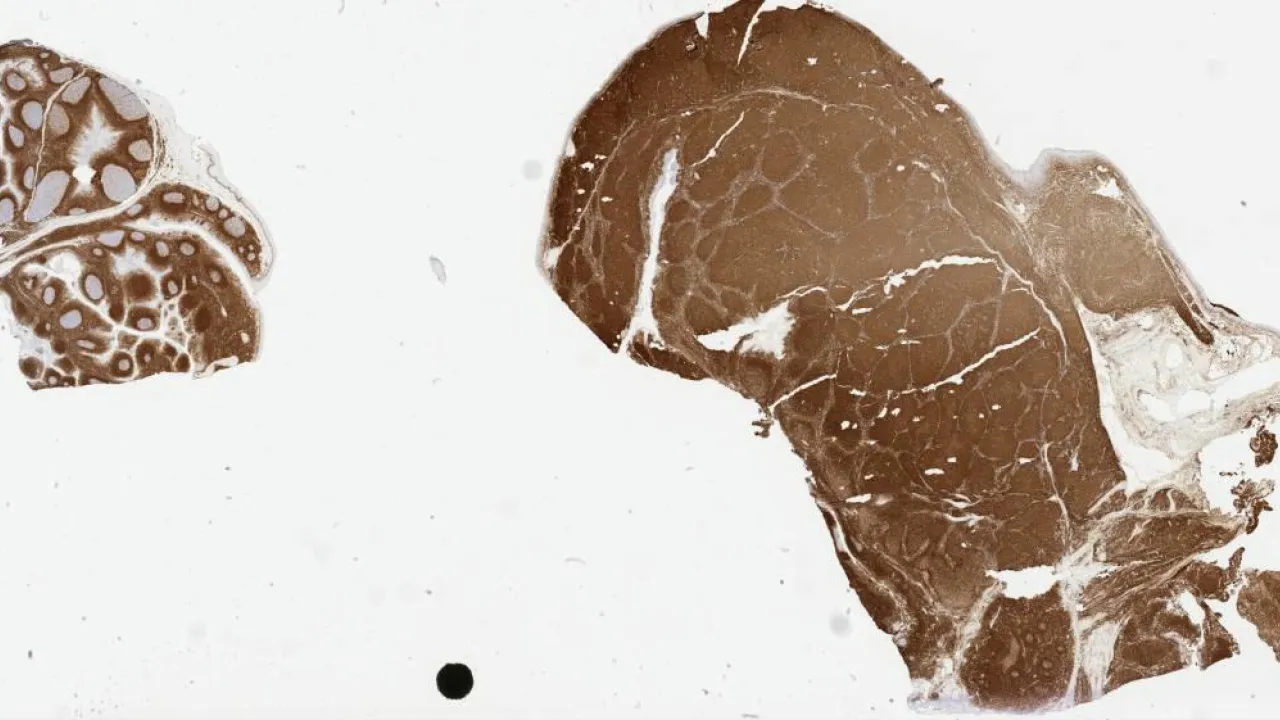

Lymph Nodes, Mantle cell lymphoma, cyclin D1 stain